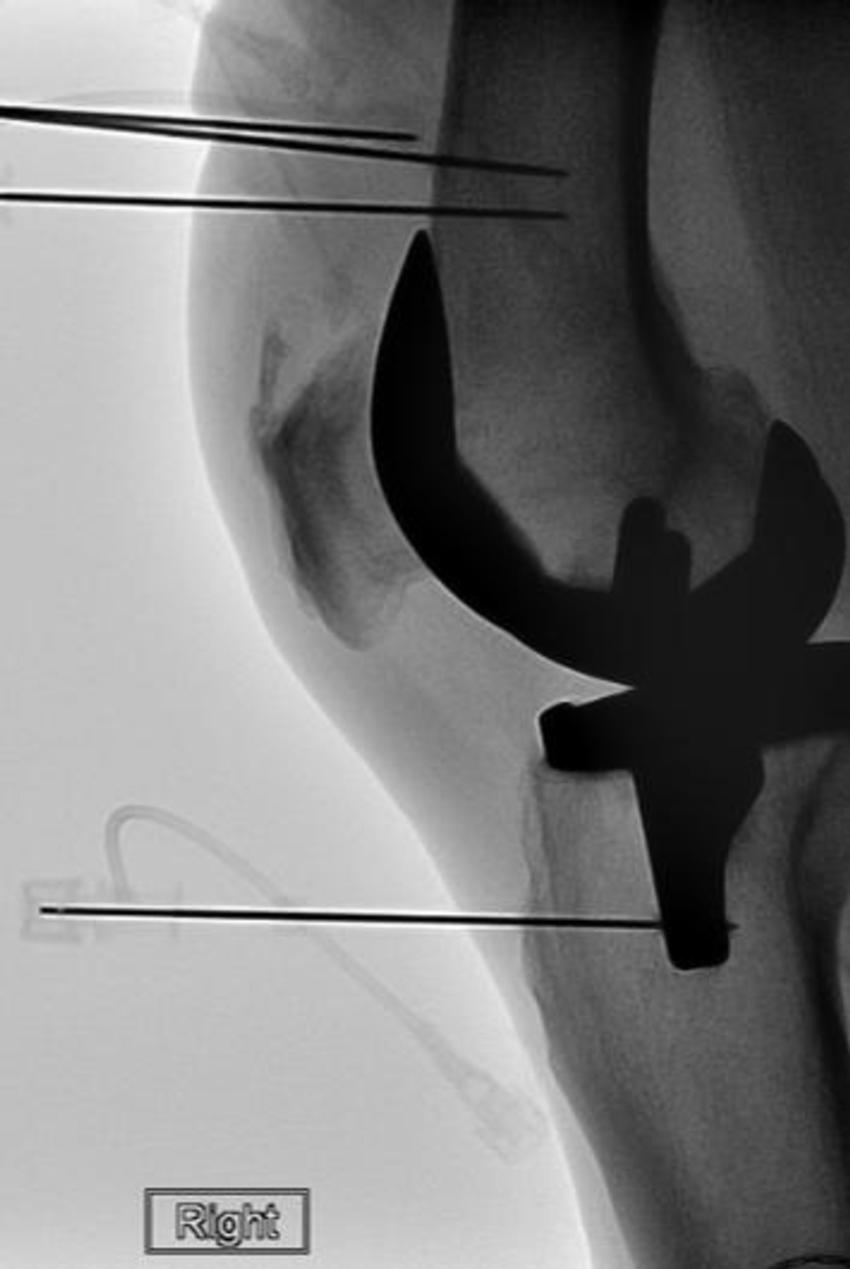

A procedure called cooled radiofrequency ablation (C-RFA) offers hope for these patients. The procedure involves insertion of an introducer needle around the knee under local anesthesia targeting specific nerve locations. A probe is then guided through the introducers. The tip of the probe imparts a low voltage current (radiofrequency) to the deep sensory nerves around the knee. Water circulating through the system allows for a greater dissipation of heat from the tip of the probe.

Figure 1. Radiofrequency ablation electrode is placed into the introducer needle after the placement of the introducer needle. Positioning was verified with imaging.

Figure 2. Radiofrequency ablation electrode is placed into the introducer needle after the placement of the introducer needle. Positioning was verified with imaging.